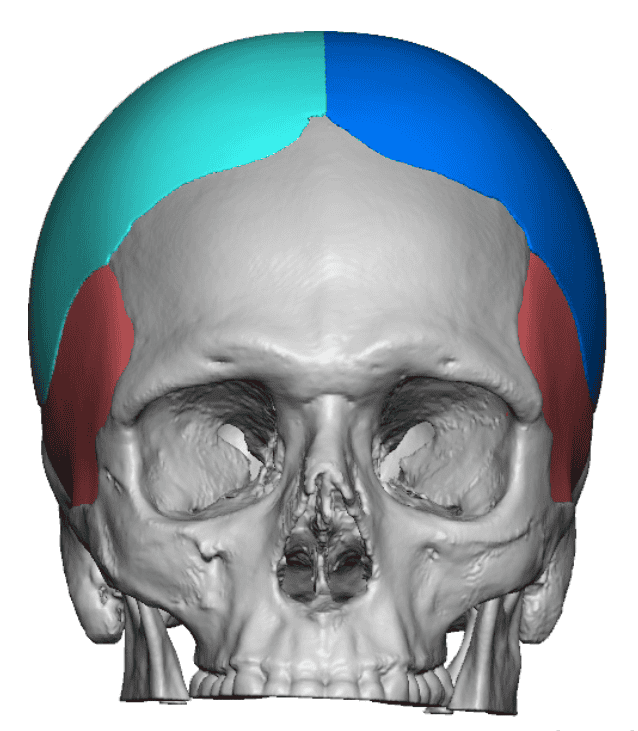

Desire for correction of head shape which has a bilateral parasagittal skull shape deformity.

Skull augmentation using a custom skull implant inserted through an existing sagittal scalp incision.

Desire for correction of head shape which has a bilateral parasagittal skull shape deformity.

Skull augmentation using a custom skull implant inserted through an existing sagittal scalp incision.